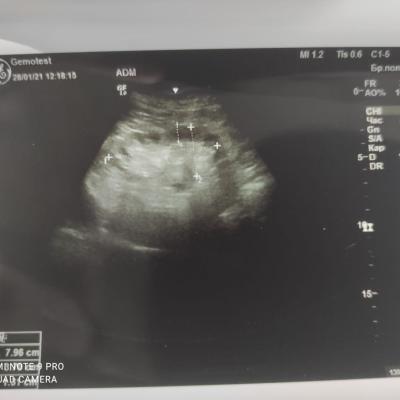

Здравствуйте! При наличии коралловидного камня правой почки(заключение УЗИ), можно предположить причиной боли нарушение уродинамики верхних мочевых путей), что, однако, не подтверждается результатами УЗИ почек( ЧЛС не расширена). Другая, наиболее вероятная возможная причина "боли в боку" - может быть патология опорнодвигательного аппарата. Необходимо проконсультироваться с неврологом и урологом очно, и согласовать возможность применения противовоспалительных, обезболивающих и спазмолитических препаратов - как первый шаг. В дальнейшем необходимо планировать возможное дальнейшее обследование и лечение. Удачи!